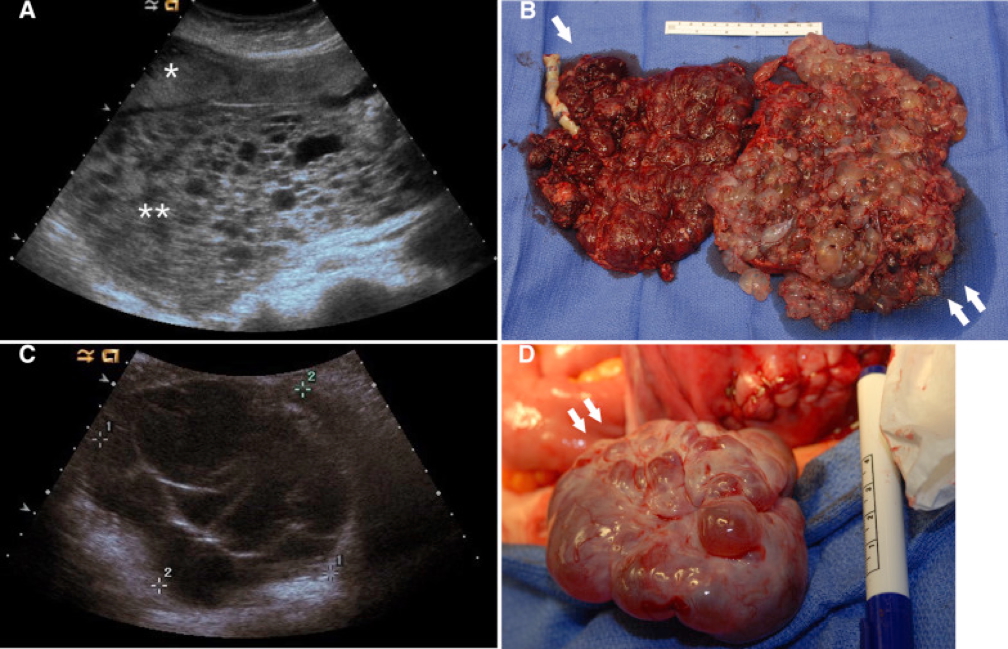

- Macroscopic:

- All chorionic villi are cystic

- No blood vessels within villi

- Grape-like clusters filling uterine cavity

- Pelvic Ultrasound:

- “Snowstorm” or “grape cluster” appearance

- Absence of a viable foetus in complete mole